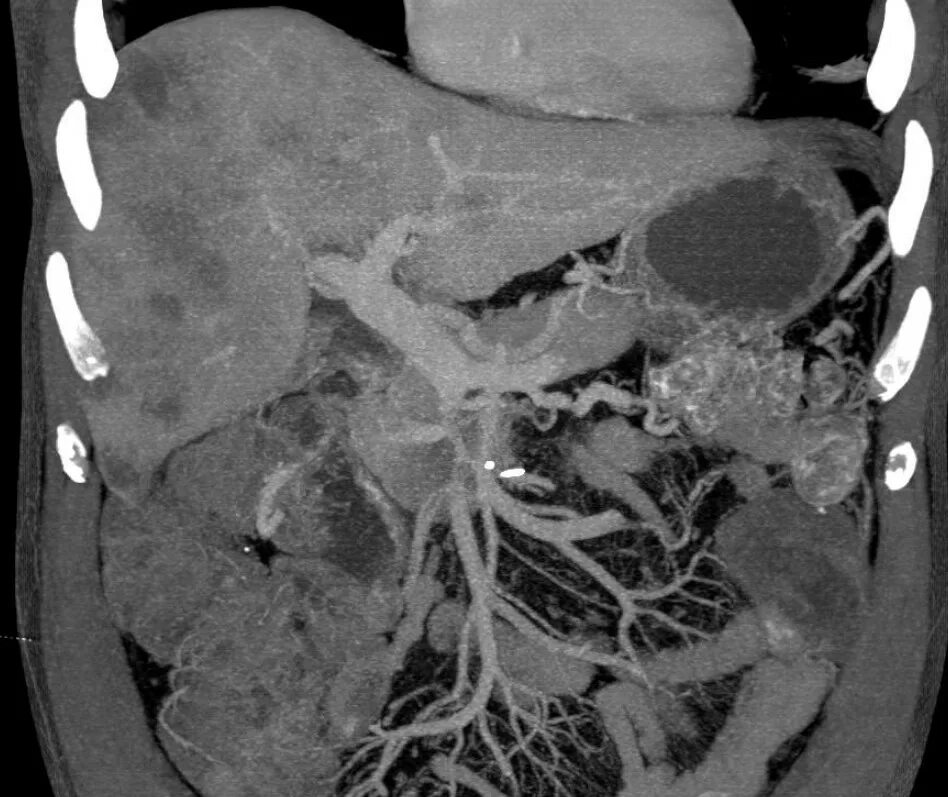

Метастазы плевры